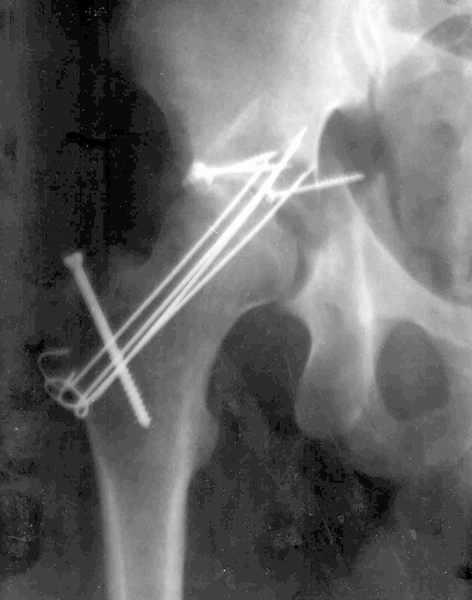

XrayCTРезультат повторной операции

В нашей клинике 23.04.03 руководитель центра А.В. Рунков выполнил выездную показательную операцию. Не смотря на то, что с момента травмы прошло 2 месяца отломки вертлужной впадины были репонированы, восстановлена конгруэнтность суставных поверхностей тазобедренного сустава, фиксация реконструктивной пластиной. Операция была выполнена на высочайшем профессиональном уровне и её результат превзошёл мои ожидания.Ранний послеоперационный период протекает без осложнений, больной "воспрял духом", чувствует себя хорошо, занимается ЛФК, разработкой движений в коленном и тазобедренном суставах, сидит, ходит на костылях. На мой взгляд представленный случай является ярким примером целесообразности телеконференций, позволяющим достичь конкретного результата. Особую благодарность хочется выразить Александру Челнокову - организатору Форума. С Уважением Андрей Стасюк